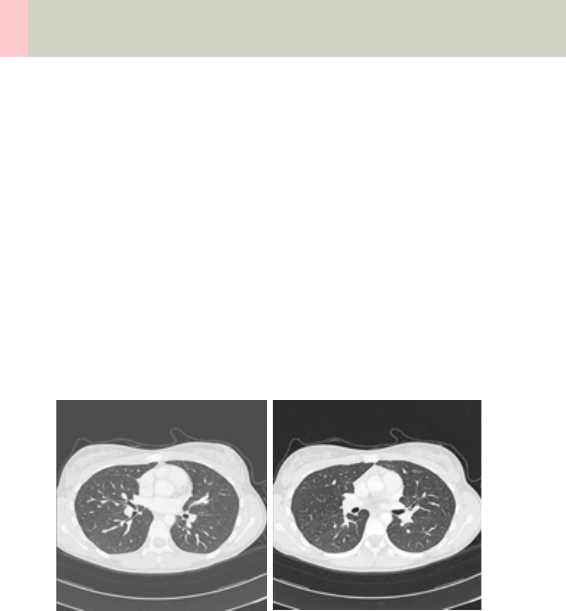

Thorax 226

•Overview 226

- General Hints 229

- Body Kernels 231

•Scan Protocols 232

- ThoraxRoutine/

ThoraxRoutine06s 232